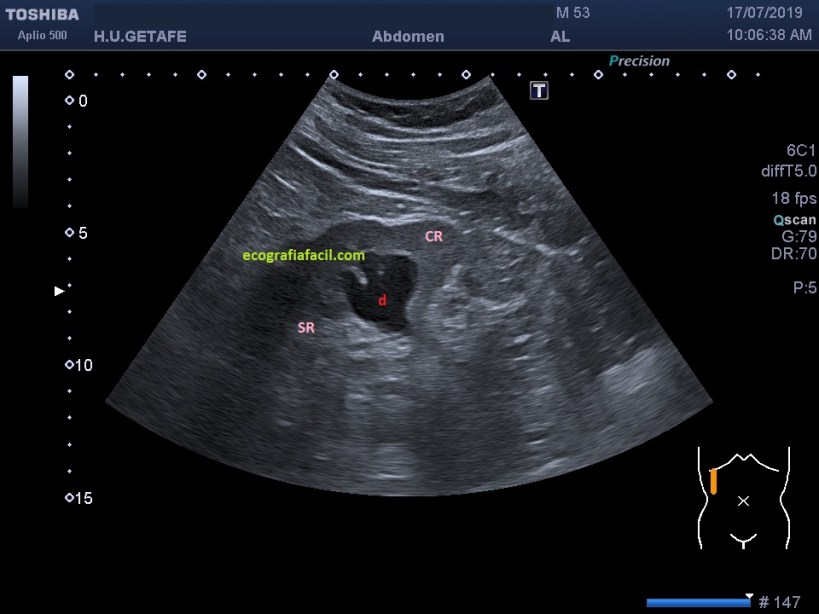

La uropatía obstructiva puede provocar una hidronefrosis que podemos confundir con un seno renal poliquístico, pero es importante buscar las interconexiones que tienen los cálices renales que son confluyentes todos en la pelvis renal, poder demostrar dicha confluencia puede ser una dato que permita a la radióloga emitir un informe en este sentido.

La manera de demostrar esto es buscando angulaciones con la sonda y movilización del paciente hasta conseguir una imagen como esta:

1

Si conseguimos demostrar la confluencia de los pielones caliciales y seguir el uréter, habremos demostrado la dilatación del sistema calicial (imagen1).